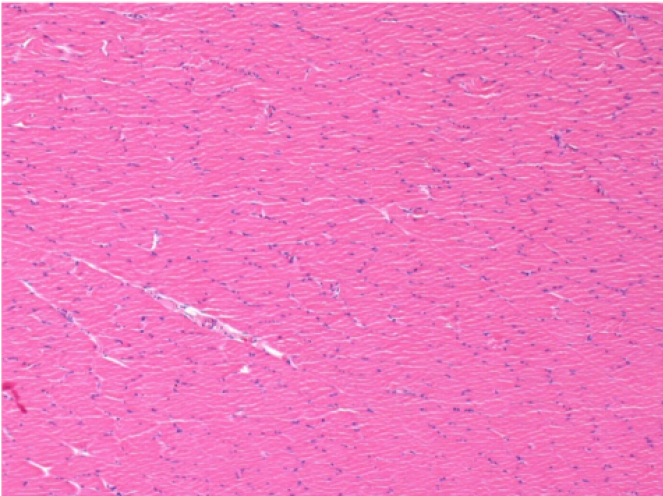

Через 3 місяці (90 днів) після ін'єкції Ендопіл 0,1 мл в правий претибіальний м'яз.